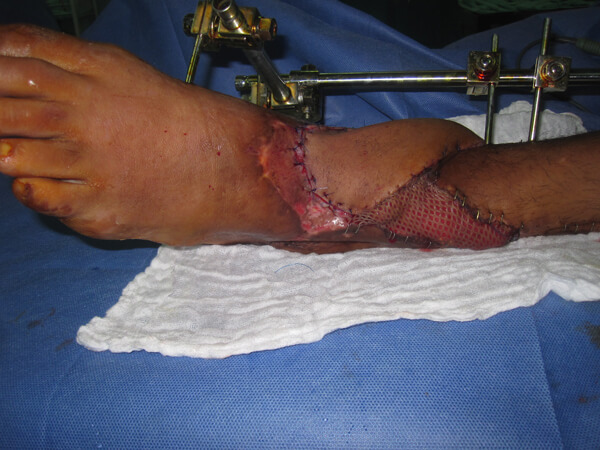

A 17-year-old adolescent sustained a GSW to his right distal leg (medial entrance wound, lateral exit wound) (Figure 7). He had a Gustilo IIIc [5,6] compound fracture (Figure 8). Acutely, the posterior tibial artery was ligated, tissues debrided and an external fixator placed. Two further soft tissue debridements were performed and unfortunately, the medial wound was closed. There was total loss of function in the peroneal and posterior tibial nerves.

Figure 7: GSW to the distal third right leg: medial entrance wound and lateral exit wound.

Figure 8: X-ray right leg: Gustilo IIIc comminuted, compound fracture

of distal third tibia and fibula with bone gap.

He presented 11 days post injury, with a history of a pyrexia and foul fluid seeping from the closed medial wound (Figure 9). He was taken immediately to theatre. All wounds were opened. Devitalised tissue was obvious as soon as the medial sutures were released (Figure 10). In view of the bone, muscle and neurovascular injury, along with contamination and symptoms of infection, amputation was considered the best modality of treatment but the boy refused his consent. Complete debridement of all non-viable tissue and through washout was performed. All wounds were left open. Broad-spectrum antibiotics were commenced: bone and tissue cultures were sent. A discussion with him and his parents was organised immediately to propose amputation.

Consent for amputation was refused again. It was therefore agreed to give the limb one chance of salvage surgery. A clear understanding was given that should sepsis occur, the boy should undergo amputation. If the limb salvage were successful, the function would be poor: an insensate, shortened leg.

Acute shortening and adjustment of the external fixator was followed by the raising of a fasciocutanteous flap on a single proximal perforator. The flap rotated easily to cover the fracture site. The donor site and any remaining medial and lateral soft tissue wounds were closed using SSG (Figure 11).

Figure 11: Medial, proximally based perforator-plus flap is used to cover exposed bone after thorough

debridement, washout and bone shortening. Skin graft covers the flap donor site and lateral wound.